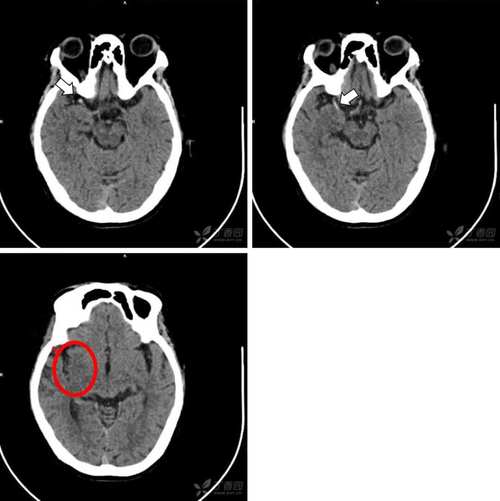

- 脑干、小脑等后颅窝的梗死: 由于颅骨的伪影干扰,CT对这些区域的显示效果较差,容易漏诊。

最重要:排除脑出血

- 脑梗死和脑出血的治疗原则完全相反,前者需要紧急溶栓或取栓,而后者绝对禁止,在给患者使用任何溶栓药物之前,必须先做一个CT检查,明确没有脑出血,这是医疗安全的“底线”。

识别其他病因

- CT可以发现可能导致类似卒中症状的其他疾病,如脑肿瘤、硬膜下血肿、脑脓肿等。